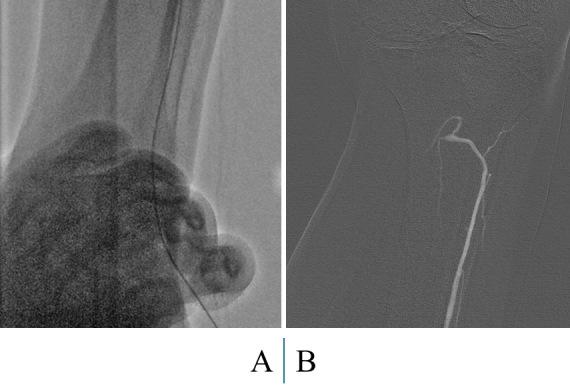

Endovascular treatment for patients with lower extremity artery disease is conducted worldwide due to its efficacy. Many studies have shown durability for patients with intermittent claudication, and various guidelines have shifted to the use of endovascular treatment. However, clinical outcomes in patients with chronic limb-threatening ischemia who undergo endovascular treatment have not been fully investigated. Generally, chronic limb-threatening ischemia cases have complex lesions such as small vessels, severe calcification, poor runoff vessels, chronic total occlusion, and long lesions, which result in poor outcomes. Thus, endovascular treatment for chronic limb-threatening ischemia cases remains challenging, despite the many technical and device advances. In 2019, the Global Vascular Guidelines were proposed for the treatment of patients with chronic limb-threatening ischemia. Here, we review previous guidelines and reports of patients with lower extremity artery disease who underwent endovascular treatment.

由于其有效性,下肢动脉疾病患者的血管内治疗在全球范围内开展。许多研究表明,间歇性跛行患者接受该治疗后效果持久,各种指南也已转向采用血管内治疗。然而,接受血管内治疗的慢性肢体威胁性缺血患者的临床结局尚未得到充分研究。一般来说,慢性肢体威胁性缺血病例存在复杂病变,如小血管、严重钙化、流出道血管不佳、慢性完全闭塞和长病变,这些都会导致预后不良。因此,尽管有许多技术和设备进展,慢性肢体威胁性缺血病例的血管内治疗仍然具有挑战性。2019年,针对慢性肢体威胁性缺血患者的治疗提出了《全球血管指南》。在此,我们回顾先前关于接受血管内治疗的下肢动脉疾病患者的指南和报告。